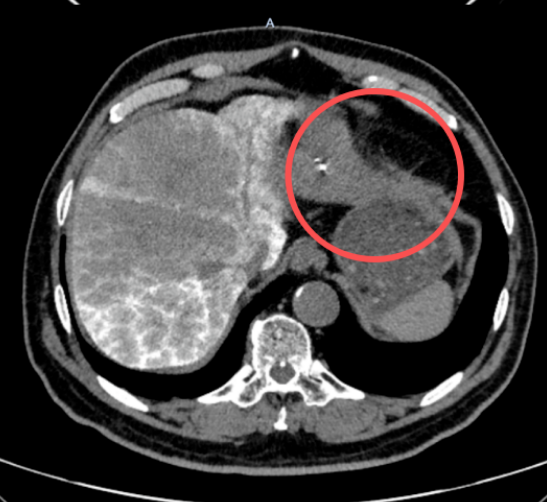

近日,长春国文医院介入治疗科刘维民主任团队,成功为一名肝恶性肿瘤患者实施靶免联合介入治疗。团队以精准化、个体化的诊疗理念,将靶向治疗与免疫治疗、微创介入技术有机结合,有效控制患者病情,使肝脏病灶从初始的90*78mm大幅缩小至29*16mm,为肝恶性肿瘤患者带来了更优质的诊疗希望。

患者杨某(化名)体检中发现肝脏恶性病灶,大小达90*78mm。面对突如其来的病情,杨某及家属辗转多家医院后,慕名来到长春国文医院介入治疗科寻求治疗。

经系统治疗后,患者杨某身体状况逐步好转,不适症状缓解。近期复查显示,肝脏肿瘤病灶已从90*78mm缩小至29*16mm,病灶体积缩减,病情得到理想控制。拿到复查结果时,患者及家属难掩激动,对介入治疗科医护团队连连致谢。